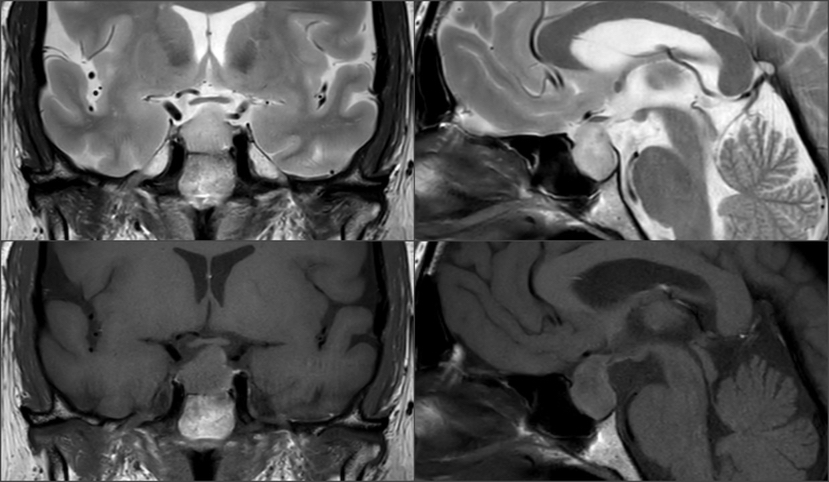

影像资料

Knosp1级肿瘤,鞍隔被肿瘤推挤向上,冠状位略呈“雪人征”,术中鞍隔可能塌陷 T2信号较为均质,考虑肿瘤有一定韧性 垂体柄偏向左侧,残存垂体左侧更多,鞍隔面、鞍底面亦有薄层受压垂体组织,术中需注意保护,亦有助于辨认肿瘤与垂体之间的分界面